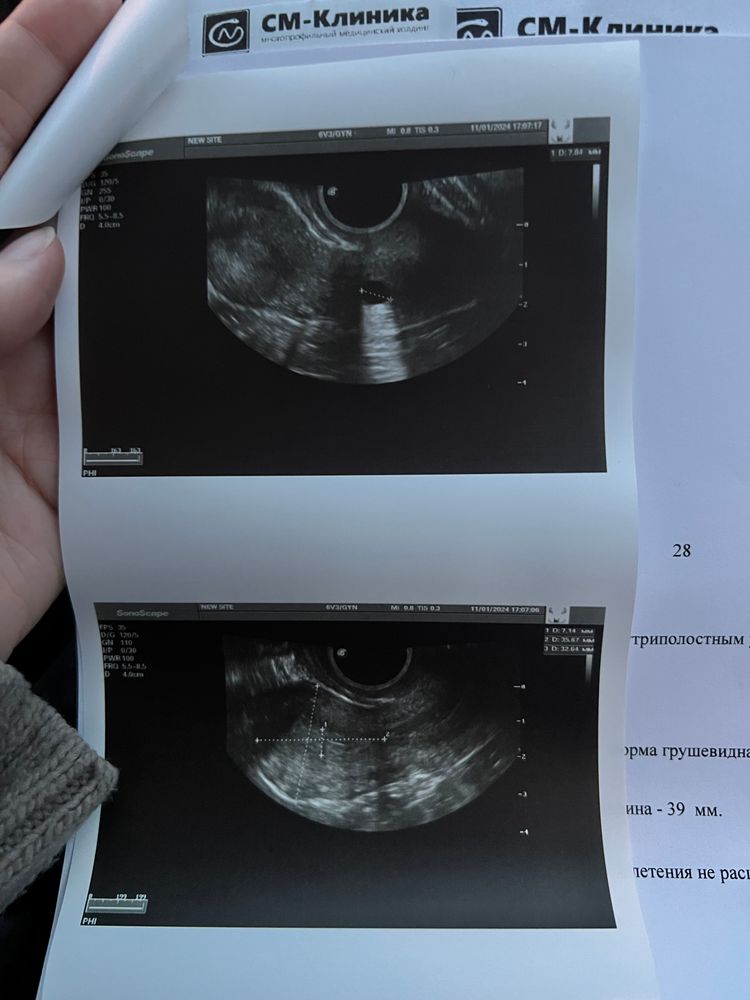

Виктория , вот заключение киста шейки матки Изображение

Мари, извиняюсь не так написала вот заключение Изображение